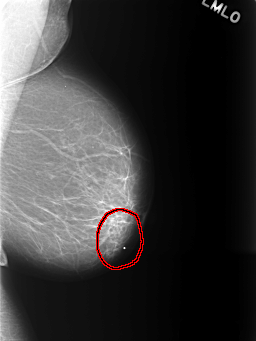

C_0401_1.RIGHT_MLO

FILE: C_0401_1.LEFT_MLO.OVERLAY

TOTAL_ABNORMALITIES 1

ABNORMALITY 1

LESION_TYPE MASS SHAPE FOCAL_ASYMMETRIC_DENSITY MARGINS ILL_DEFINED

ASSESSMENT 3

SUBTLETY 5

PATHOLOGY BENIGN

TOTAL_OUTLINES 1

BOUNDARY